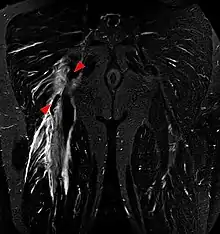

Imaging the hamstring muscles is usually performed with an ultrasound and/or MRI.[9] The biceps femoris is most commonly injured, followed by semitendinosus. Semimembranosus injury is rare. Imaging is useful in differentiating the grade of strain, especially if the muscle is completely torn.[10] In this setting, the level and degree of retraction can be determined, serving as a useful roadmap prior to any surgery. Those with a hamstring strain of greater than 60mm in length have a greater risk of recurrence.[11]